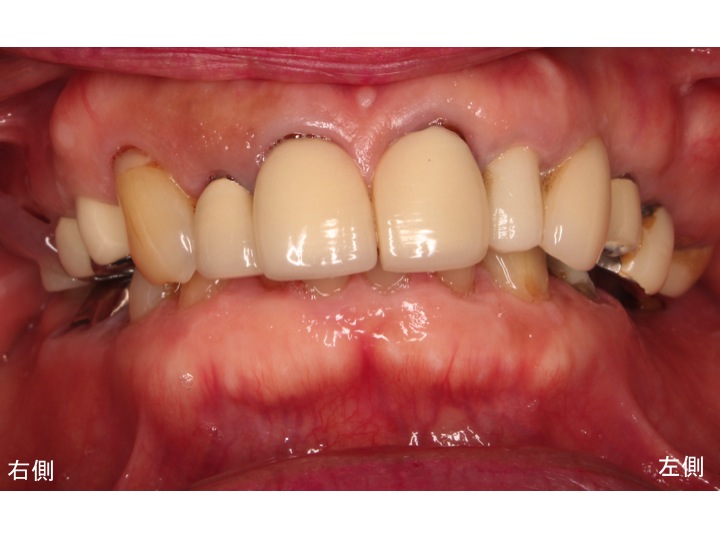

以下が先日行った手術直後です。

インプラントが骨としっかりとくっついたら

奥歯の歯根破折している歯を抜歯します。

そして、抜歯と同時にインプラント部分に仮歯を作成します。

こうしたことによって、

歯がない期間を完全に無くします。